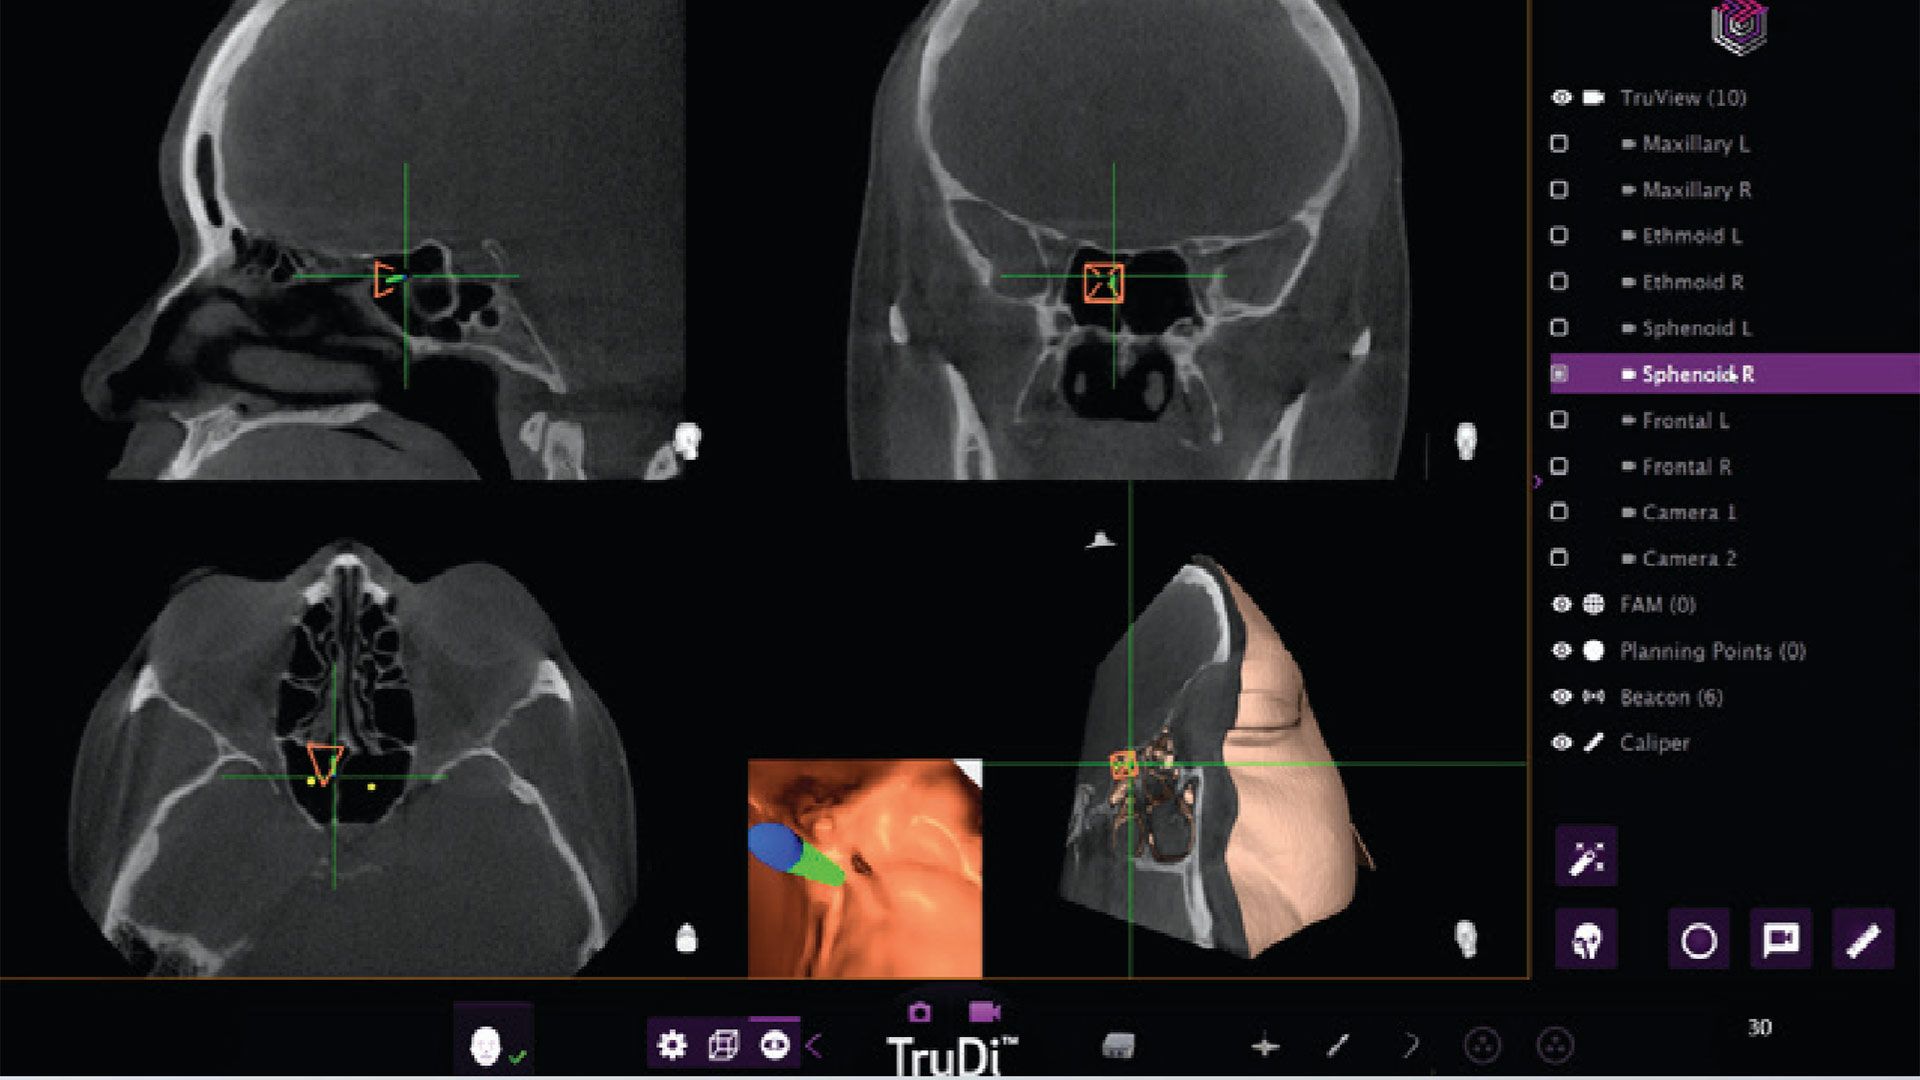

- https://www.tomshardware.com/tech-industry/artificial-intelligence/adding-ai-to-sinus-surgery-system-saw-malfunctions-rocket-from-eight-to-100-incidents-according-to-new-investigation-skull-puncturing-errors-are-the-stuff-of-nightmares#main